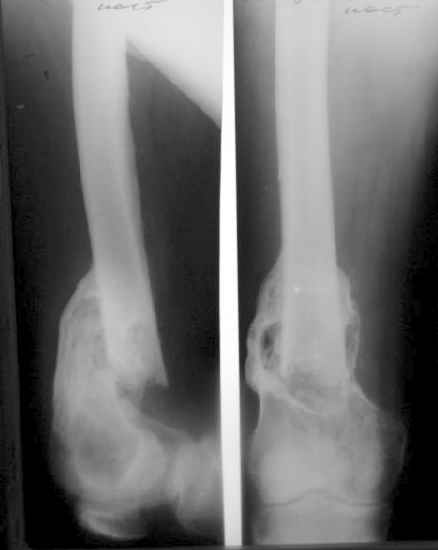

Пациент 53 лет травма 25.11.02. в салоне автомашины, получил множественные переломы ребер с ушибом легких и гемопневмотораксом, ротационно нестабильное повреждение таза: перелом боковых масс крестца, разрыв лонного сочленения, оскольчатый поперечный юкстатектальный перелом левой вертлужной впадины с центральным вывихом бедра и сегментарным переломом головки, перелом крыла правой подвздошной кости. Открытый многооскольчатый перелом костей правого предплечья, перелом правого бедра в нижней трети, перелом надколенника слева, перелом лодыжек левой голени с переломом заднего края левой большеберцовой кости подвывмхом стопы.Бедро срослось на вытяжении, лодыжки в гипсе, предплечье в аппарате. Под наше наблюдение попал 25.03.03. Выполнен чрескостный остеосинтез таза, с постепенной коррекцией положения отломков, затем 28.04.03 реконструкция вертлужной впадины для эндопротеза, синтез лонного сочленения. В настоящее время ходит с костылями, беспокоят боли в левом тазобедренном суставе, прогрессирует деформация головки. То есть в ближайших планах - эндопротезирование этого сустава. Однако смущает ряд моментов: В частности, на стороне предполагаемого эндопротезирования (левой) имеется разрыв собственной связки ниже надколенника, который подпаян к бедру (видно на фото сидя), то есть активного разгибания голени нет. А на правой стороне имеется штыкообразная деформация бедра, нет полного разгибания коленного сустава, хотя конечность опороспособна; ортопедическое укорочение 3 см.Вопросы: Что делать с левым надколенником и 4-главой мышцей? Восстанавливать ли ось и длину правого бедра? Если не трогать правое бедро, то на сколько компенсировать укорочение при эндопротезировании?